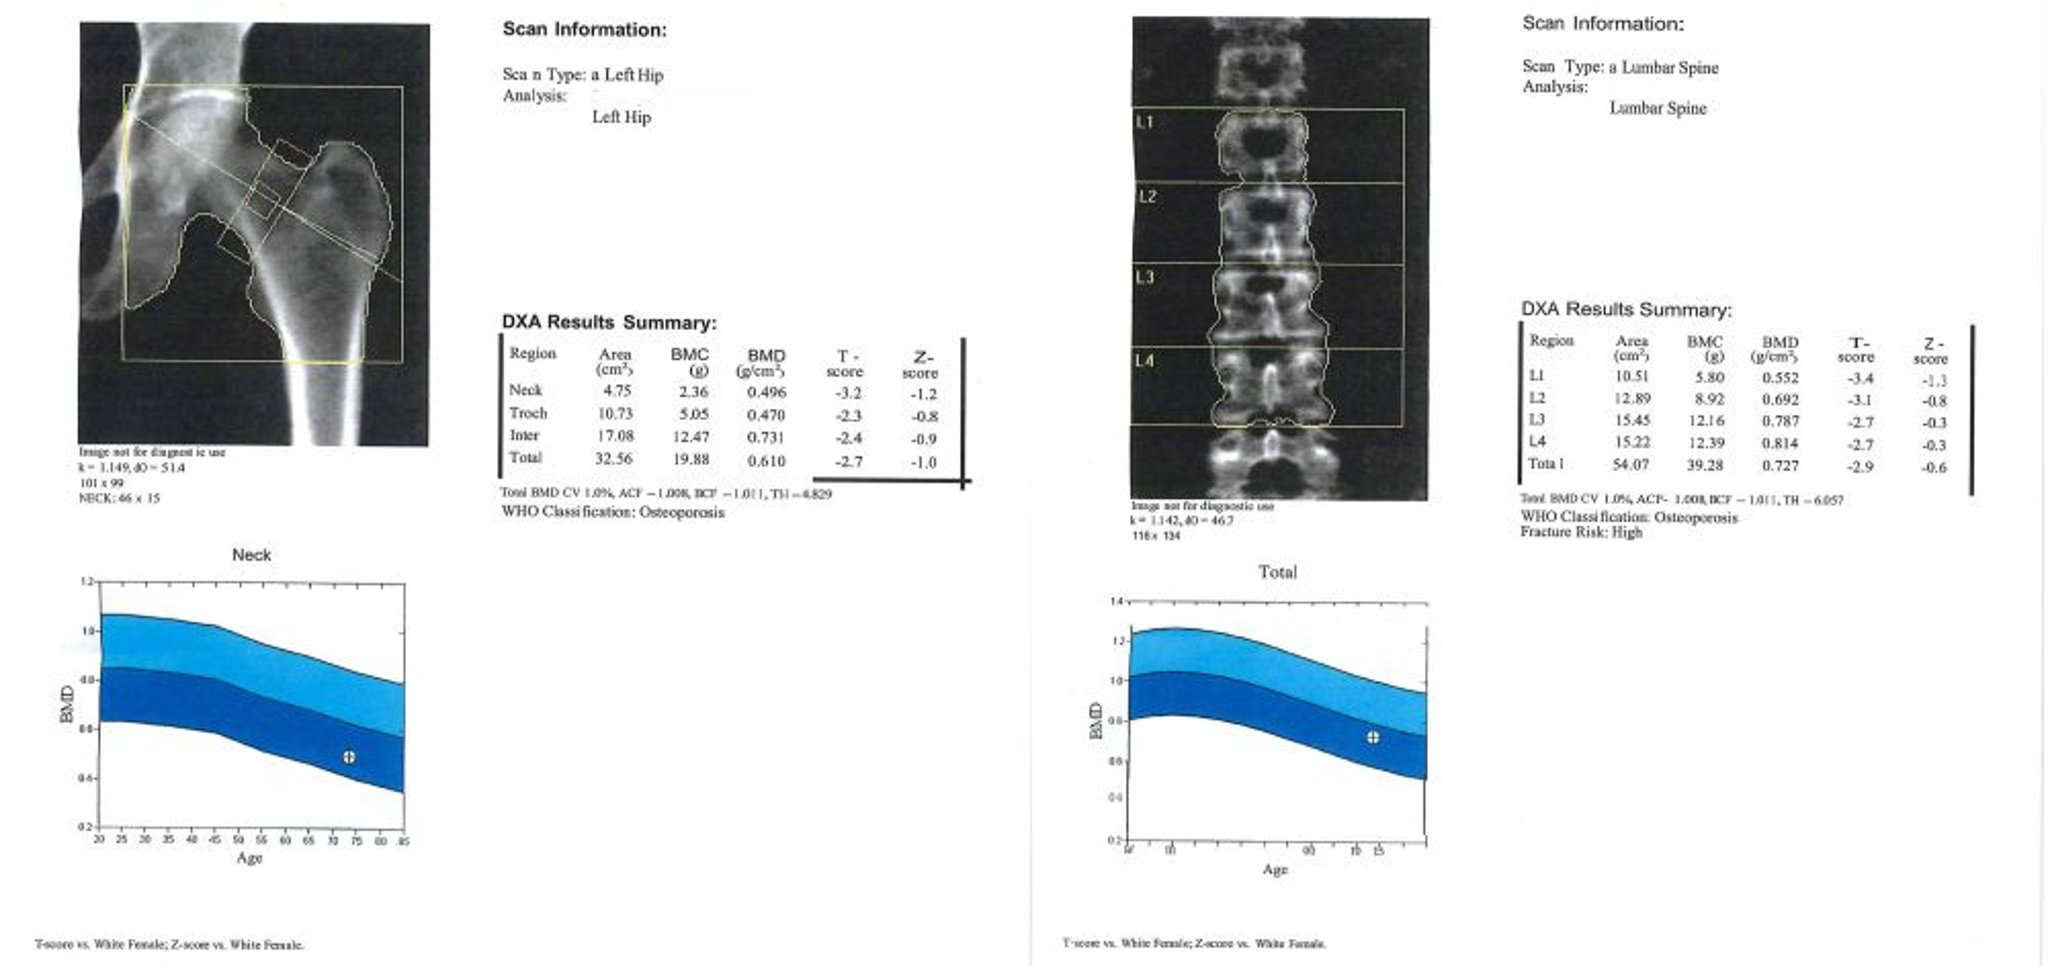

DXA-Scan

Dieses Bild ist ein Beispiel für einen DXA-Scan-Bericht. In der grafischen Darstellung steht der hellblaue Bereich für Osteopenie und der dunkelblaue Bereich für Osteoporose. Die Werte des Patienten werden durch das "+" - Zeichen innerhalb des Kreises in jedem Diagramm dargestellt.

Image courtesy of Marcy B. Bolster, MD.